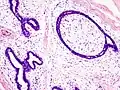

Closeup of a fibroadenoma of the breast

Macroscopic

Approximately 90% of fibroadenomas are less than 3 cm in diameter. However, these tumors have the potential to grow reaching a remarkable size, particularly in young individuals. The tumor is round or ovoid, elastic, and nodular, and has a smooth surface. The cut surface usually appears homogenous and firm, and is grey-white or tan in colour. The pericanalicular type (hard) has a whorly appearance with a complete capsule, while the intracanalicular type (soft) has an incomplete capsule.[9]

Fibroadenoma of the breast is a benign tumor composed of a biplastic proliferation of both stromal and epithelial components.[12][13] This biplasia can be arranged in two growth patterns: pericanalicular (stromal proliferation around epithelial structures) and intracanalicular (stromal proliferation compressing the epithelial structures into slit-like spaces).

These tumors characteristically display hypovascular stroma compared to malignant neoplasms.[2][14][9] Furthermore, the epithelial proliferation appears in a single terminal ductal unit and describes duct-like spaces surrounded by a fibroblastic stroma. The basement membrane is intact.[15]